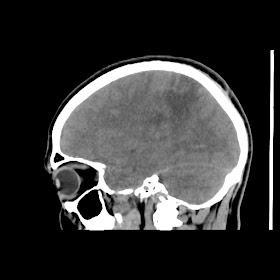

A 35 years old man CT head